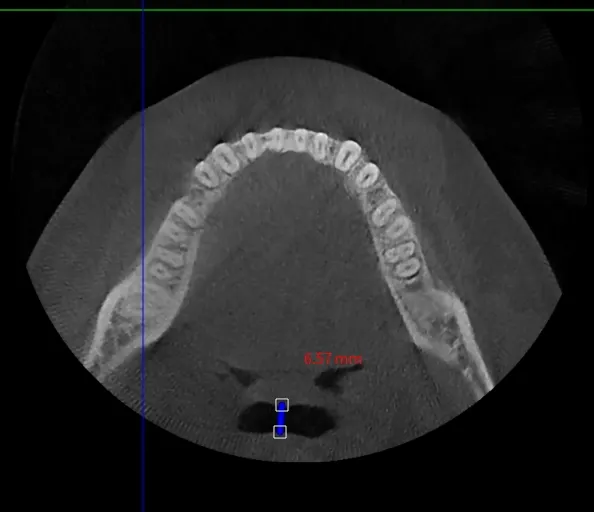

필요시 경부 CT (Airway CT) 촬영을 통해 추가적인 해부학적 문제를 진단합니다.